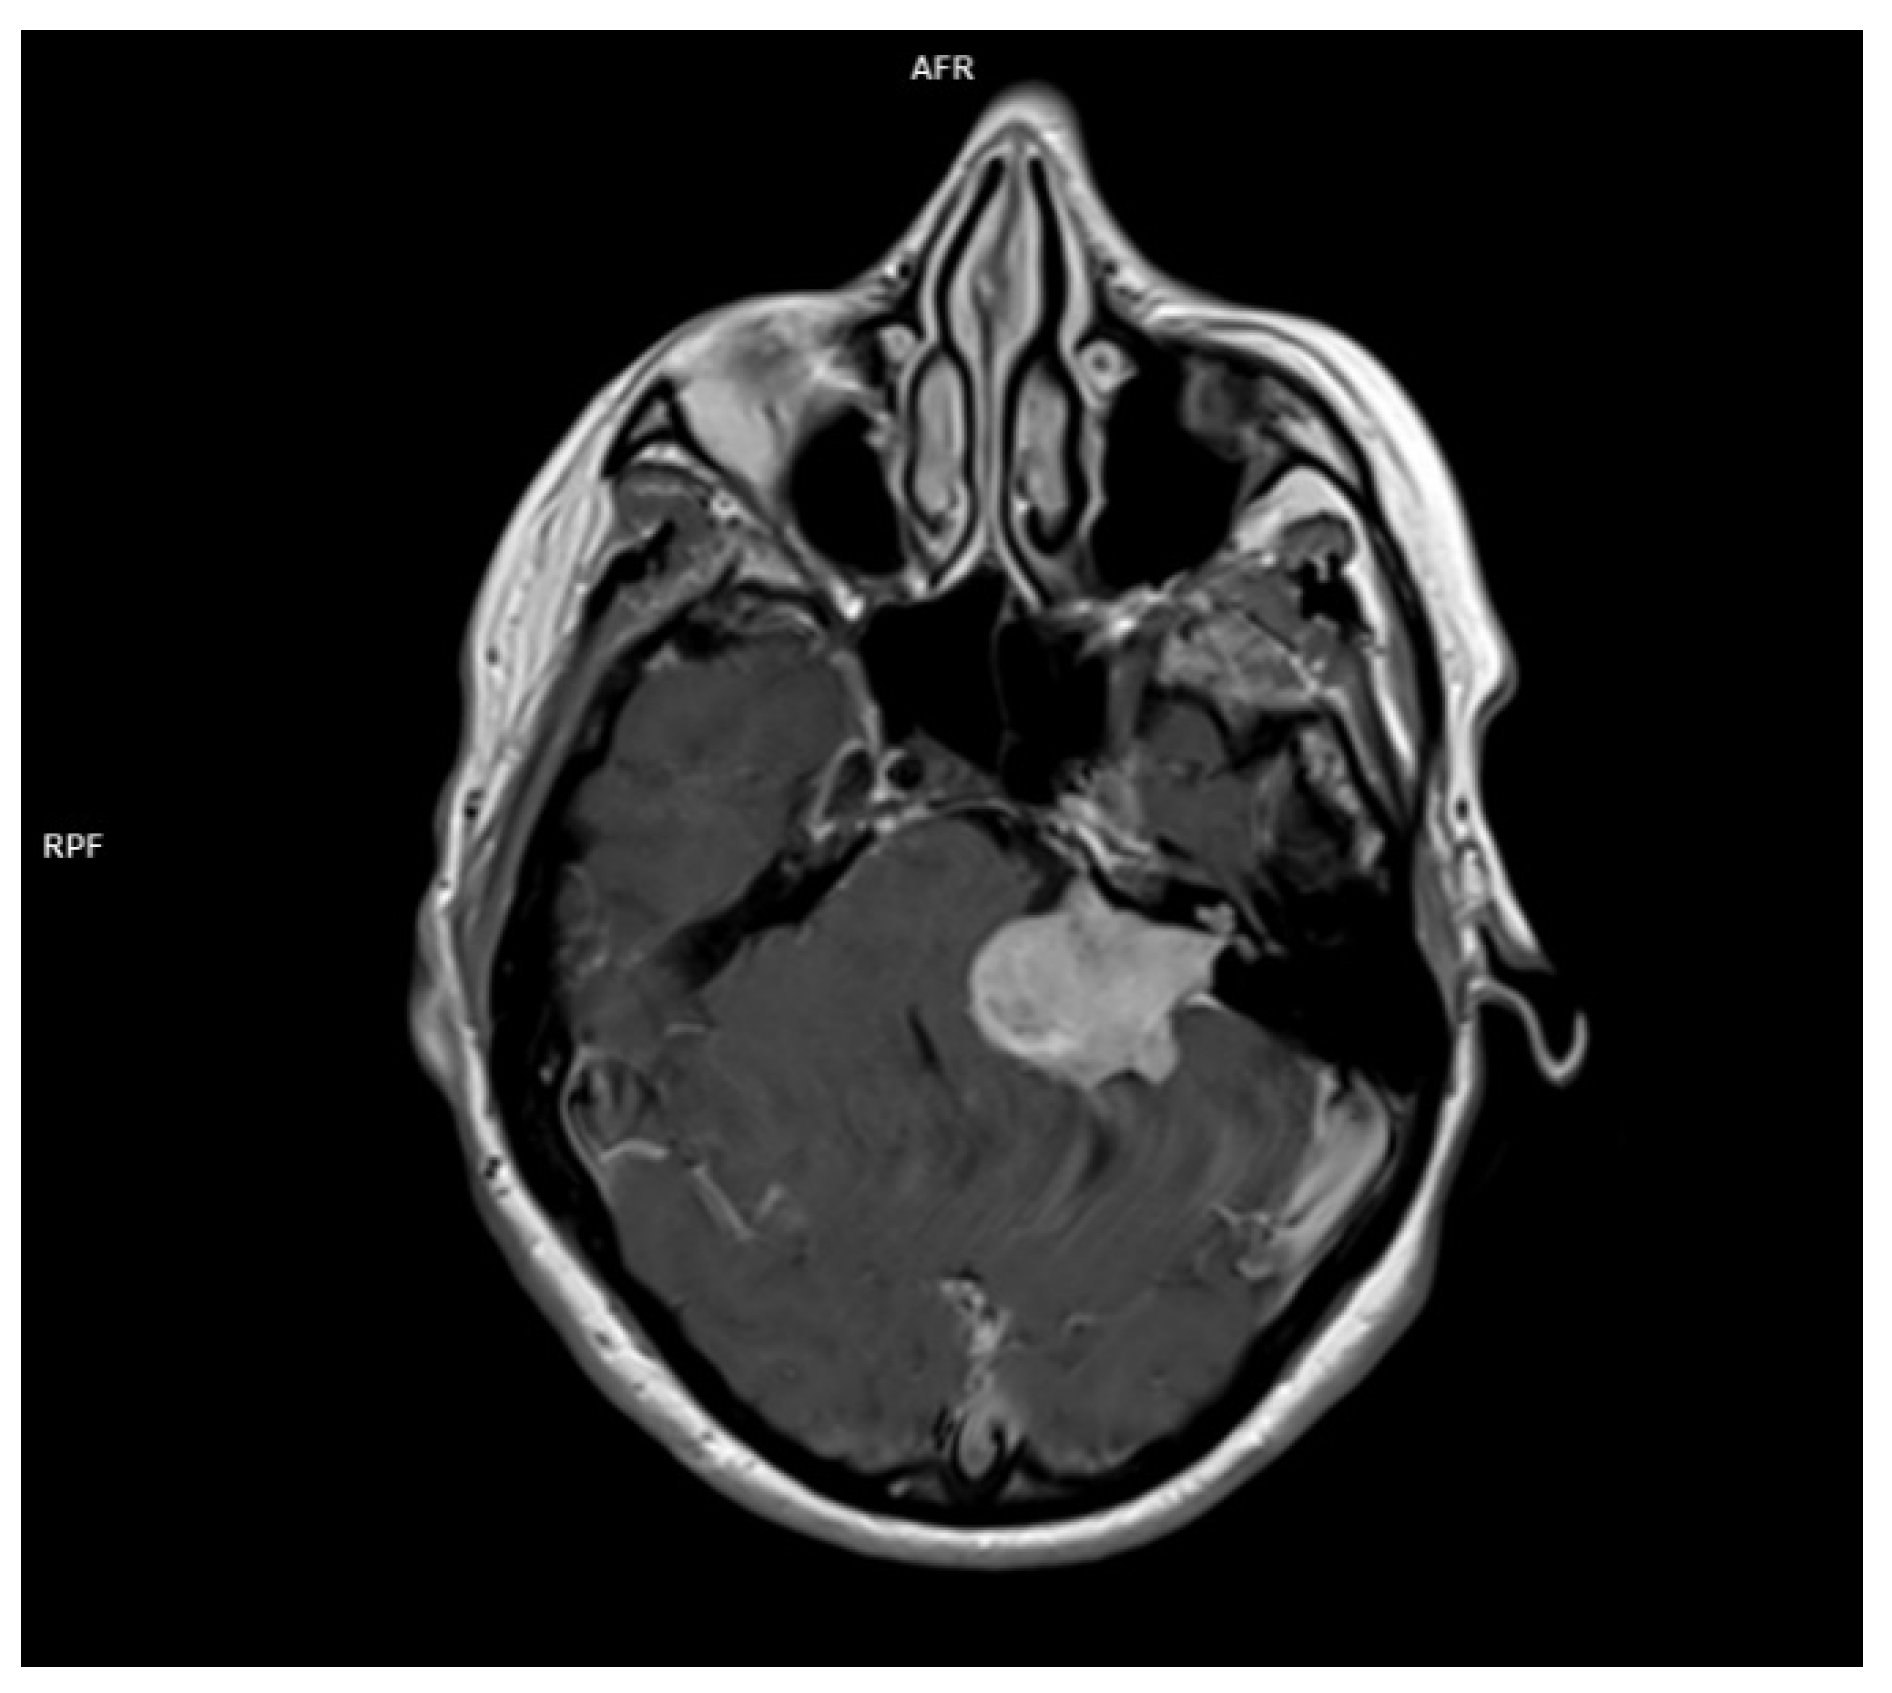

For the radiologic evaluation of vestibular schwannomas MRI and CT scans are considered. MR is the preferred technique use to characterize, therapeutic planning and post therapeutic evaluation for acoustic neuromas. CT is used whenever MRI is contraindicated for different reasons. CT may reveal internal acoustic canal enlargement or bone erosion, with contrast enhancing the lesion. In some cases, enhancement can be underwhelming especially in large, cystic tumors [62]. The lesion is hard to see especially on account of the adjacent petrous bone artifacts. MRI, particularly with contrast, is the “gold standard” [63], showing the tumor [62]as hypointense or isointense on T1 and hyperintense on T2 images, with intense contrast enhancement [64]. In Figure 2. there is the image of a huge vestibular schwannoma seen on a T1 sequence with contrast invading the cerebello-pontine angle and compressing the CNS adjacent structures. A target sign (a T2 hyperintensity circumscribing a central hypointensity) is a specific sign for a peripheral nerve sheath tumor, but it is not specific for a schwannoma.

Figure 2. MRI T1 with contrast of a left acoustic neuroma occupying the internal acoustic canal, the pontocerebellar angle compressing the CNS adjacent structures.